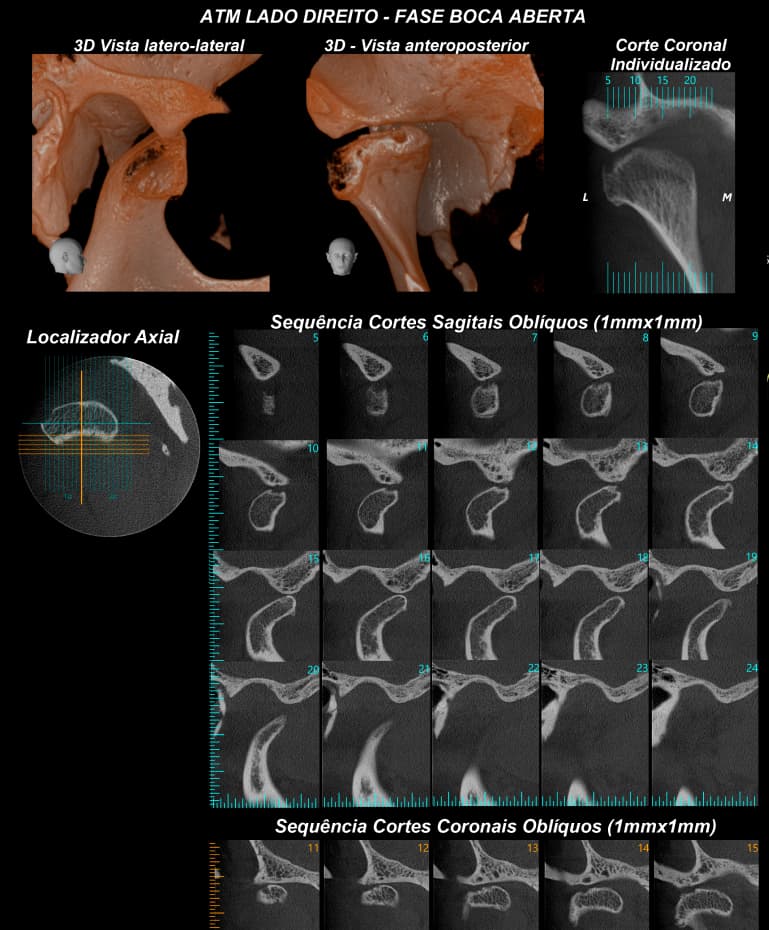

- Radiografia da ATM boca aberta e boca fechada

TOMOGRAFIA COMPUTADORIZADA DE ALTA RESOLUÇÃO por feixe Cone Bean - MORITA X800

- ATM´s